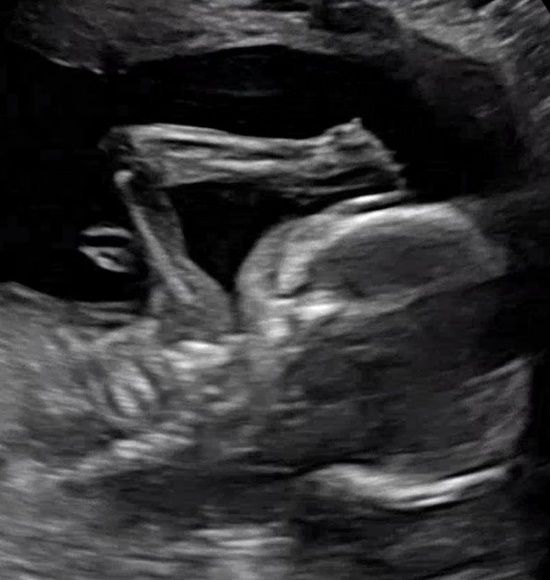

노희지는 16일 "드디어 알았어요. 한쪽 팔 이마에 올리고 있는 자세까지 저랑 똑같은 따봉이는 딸이었습니다"라고 전했다.

지난 10월 노희지는 "세상에나 이런 날이 오다니 내가 엄마라니. 따봉아 건강하게 무럭무럭 잘 커서 내년에 만나"라며 초음파 사진을 공개, 임신 소식을 전해 많은 화제를 불러모은 바 있다.